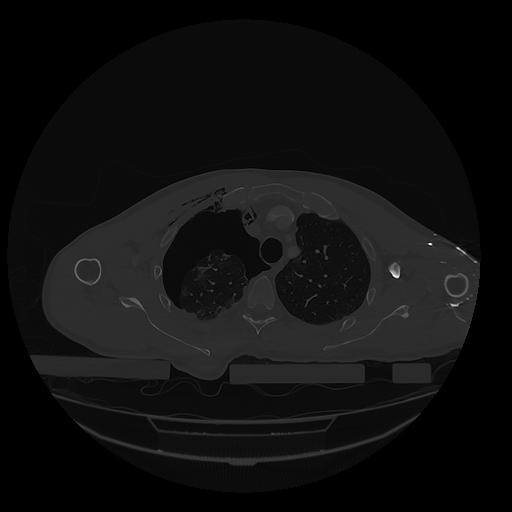

31 PULMON,CE,Vol,1.0,PULMON,,